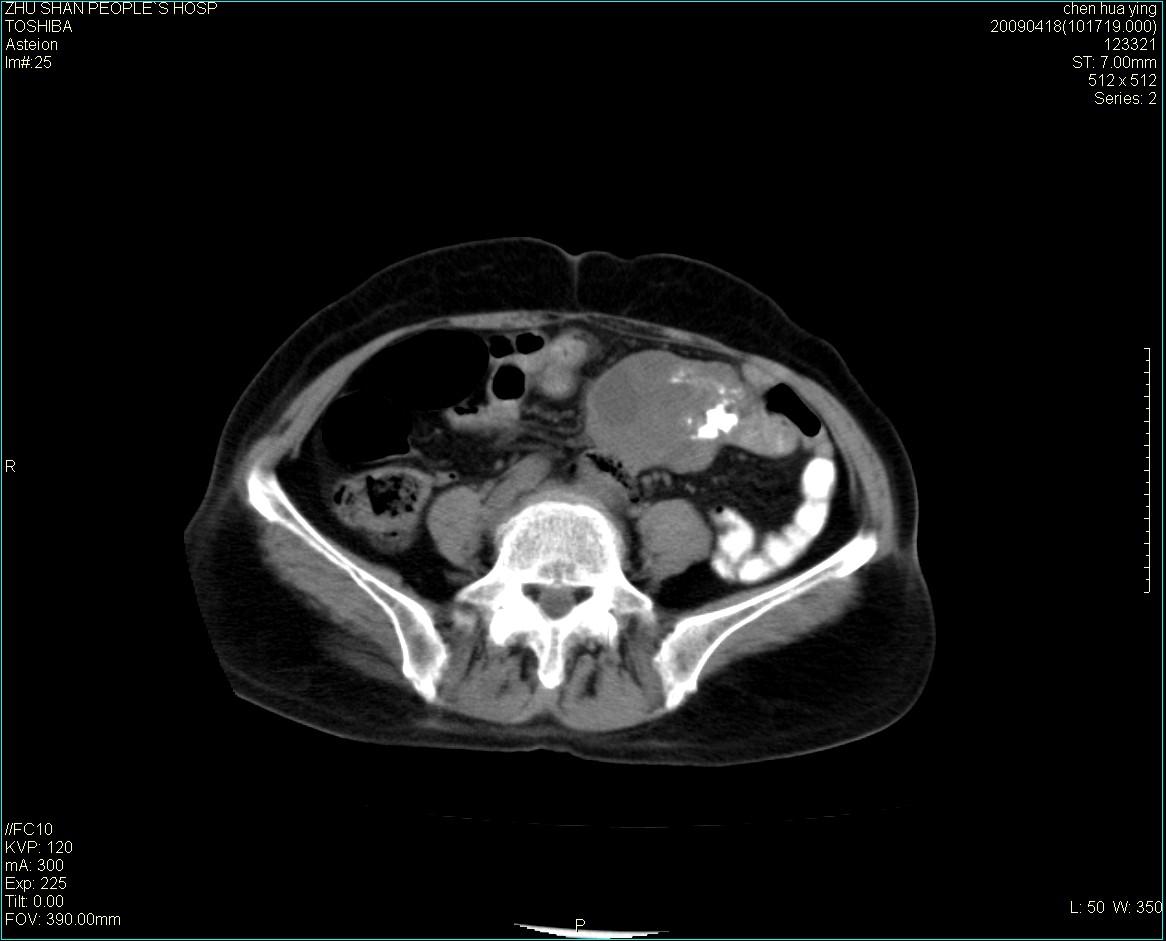

女性病人 65岁 腹部包块半年余结肠造影未见异常.

病灶略呈圆形有分叶状,上部层面呈实性,右侧见圆形低密度区,灶内见团块状钙化,病灶下方与肠管分境不清,考虑间质瘤可能性大,建议肠道准备后增强